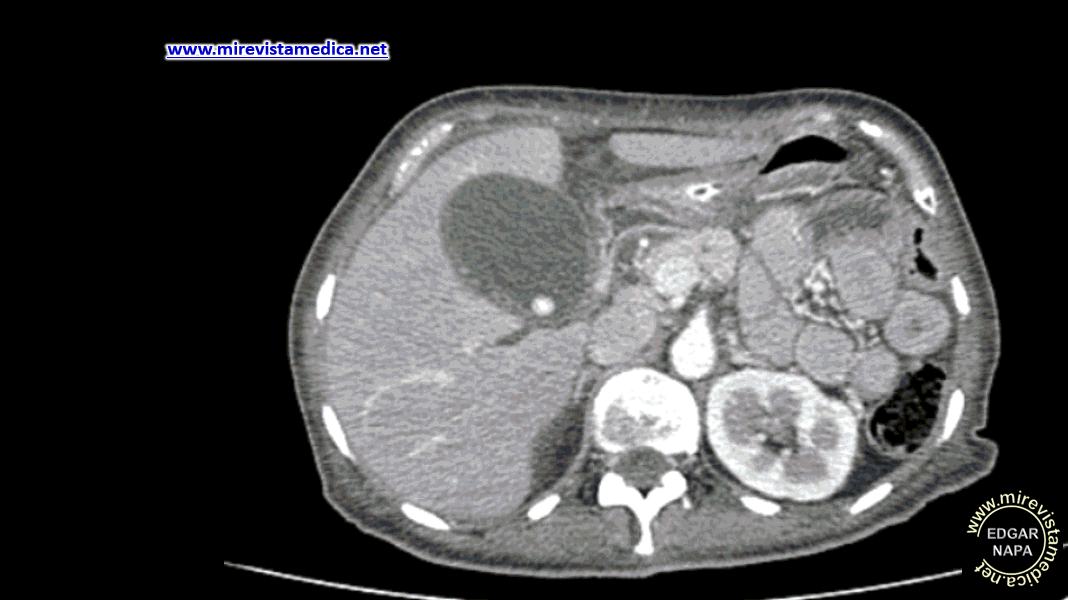

Hallazgos tomográficos en la colecistitis aguda calculosa.

- Distensión de la vesícula biliar, que es > 5 cm en el eje corto.

- Engrosamiento de pared vesicular, > 3 mm, con realce al contraste de su pared con imágenes de "hebras de grasas" de localización pericolecística.

- Calculo calcificado (15% de los casos).

- Realce al contraste del parénquima hepático adyacente.